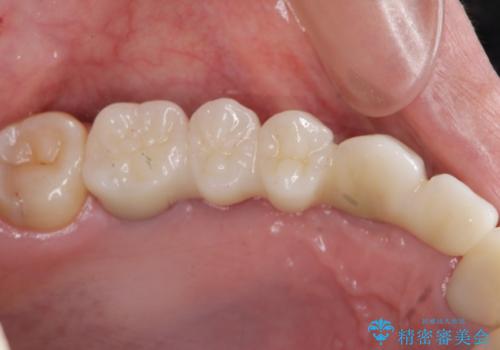

- 120万円(ストローマンインプラント×3・骨造成・チタンカスタムアバットメント×3・フルジルコニアクラウン×5)費用は治療当時の料金となります